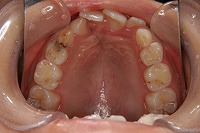

反対咬合を主訴に来院された、右側唇顎裂の10歳6ヵ月の女の子です。診断「右側唇顎口蓋裂で反対咬合を伴う」1期治療で反対咬合の解消と上顎の前歯の並びを修正しました。2期治療は抜歯をせず治療を行いました。